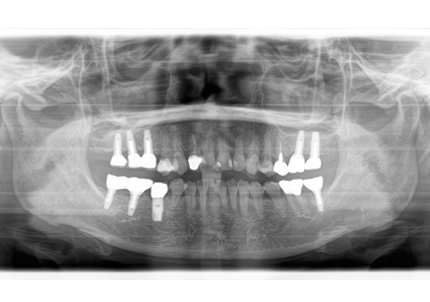

1.初診時口腔内(2007年6月30日)

2.右側上顎洞サイナスリフト後にインプラント埋入

↑ サイナスリフト術前

↑ サイナスリフト術後

3.右上インプラント補綴物装着(2009年7月24日)

↑ 右上サイナスリフト後にインプラント埋入

4.左上下7番インプラント補綴物装着(2010年5月24日)

5.右上7番インプラント(2013年11月6日)

6.右下6,7番インプラント(2017年9月15日)

7.左上6番インプラント(2021年2月21日)

8.初診より現在に至る

強い歯ぎしり、くいしばりで奥歯の歯牙破折、深い虫歯で保存不可能となり全顎治療となる。

↑ 2007年6月30日(初診)

↑ 2025年9月9日

治療後は経過良好